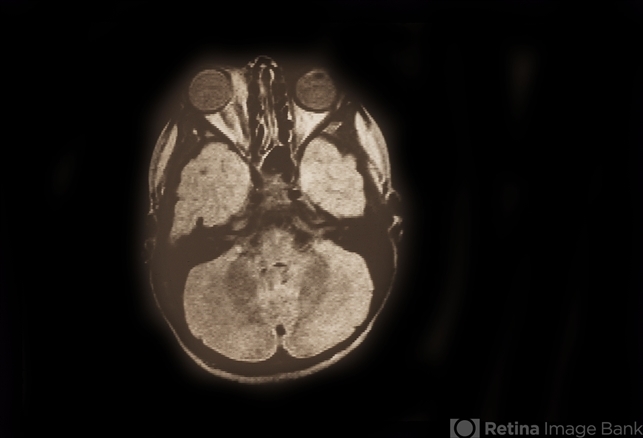

- Rhabdomyosarcoma R Orbit

- Condition/keywords

- rhabdomyosarcoma

- Four year old patient. CMC patient; embryonal rhabdo; CT, MRI, Clinical, and histology photos.